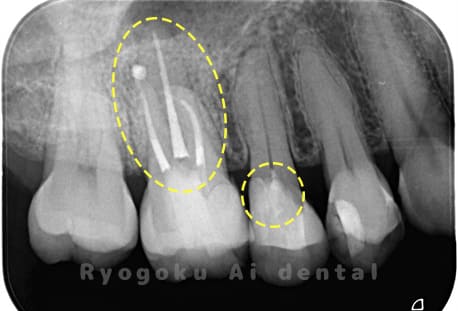

Case01

根管内の異物

- 原因

- 根管内異物(ファイル破折)による慢性根尖性歯周炎

- 治療期間

- 3ヶ月

- 治療内容

- マイクロスコープを使用した根管内異物除去並びにマイクロエンド

- 治療費用

- 121,000円(ファイル除去費用も込み)

他院で細い器具(ファイル)が根管内に破折した状態で、咬合痛を主訴に来院された患者様です。ファイルをマイクロスコープ下で除去し、根管治療を行ないました。

<リスク・副作用>

術後は痛み、腫れ、痺れなどの副作用が生じる場合があります。症状が再発する可能性があります。